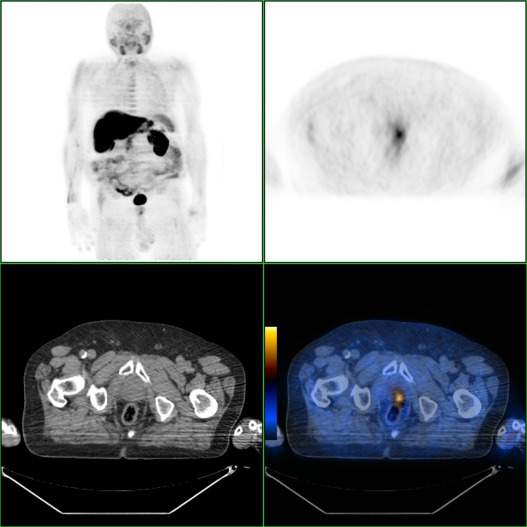

Nas Figura 1 , Figura 2 , Figura 3  ;  Figura 4 apresentam‐se 4 exames PET/CT com FCH‐F18 realizados em contexto de estadiamento inicial de CaP. Na figura 1 encontra‐se um doente apenas com doença prostática com PSA de estadiamento de 48 ng/mL. Na figura 2 apresenta‐se um doente com doença prostática e metastização ganglionar pélvica com PSA de estadiamento de 40 ng/mL. Na figura 3 , o doente apresentava doença prostática e metastização ganglionar à distância e tinha um PSA de estadiamento de 43 ng/mL. Na figura 4 o doente apresenta doença prostática e metastização óssea, e tinha uma PSA de 11 ng/mL.

Doente com CaP com PSA de 40ng/mL, com a doença prostática (A) e metástase ...

Figura 2.

Doente com CaP com PSA de 40 ng/mL, com a doença prostática (A) e metástase ganglionar ilíaca externa direita (B).